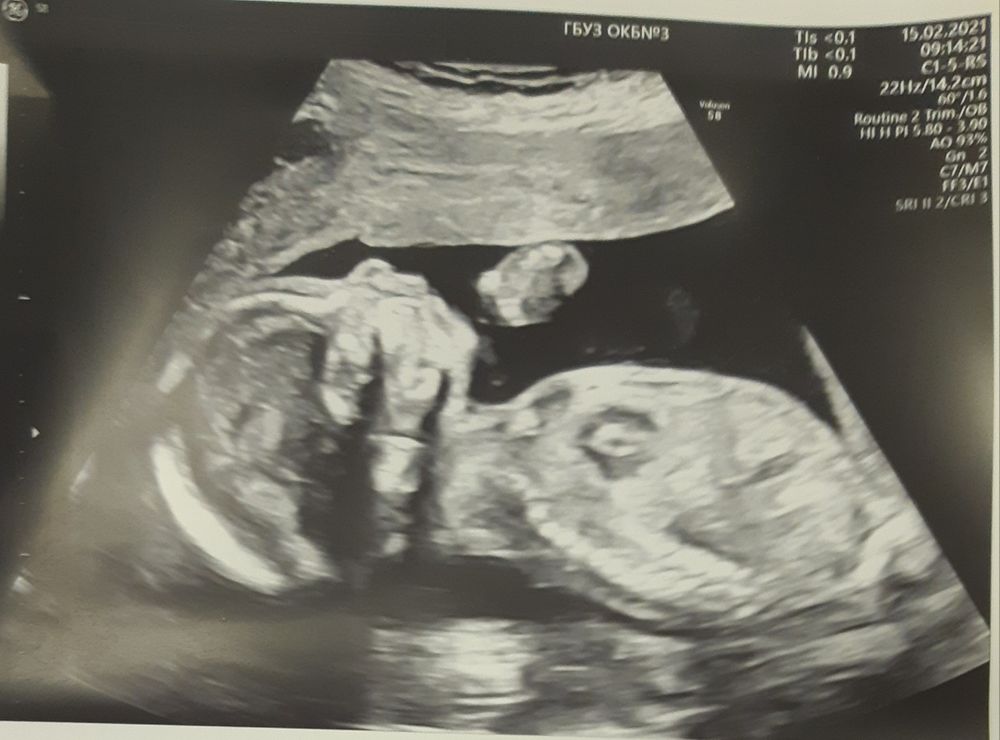

Экватор, УЗИ и тайна лопнувшего шара)))

Поздравляю вас с сыночком👶🌷🌷🌷. По фото с узи сразу поняла, что мальчик, все таки они сильно отличаются от девочек🤗

НЮША (ник в ИГ Visla79), Спасибо))) Вот муж у меня тоже сразу сказал по фото с УЗИ - да что тут гадать это пацан, а мне казалось голова такая аккуратная прям девчачья))) Мы просто с дочей 3д фото делали и не с чем сравнить вот такой профиль)

Поздравляю вас с мальчишкой! Мы в субботу лопнули шарик, рассекретили дочку:) Вы пишите, что головка на 2 недели вперед, а у нас на 19.3 головка, а все остальное на 19.6-20.3. Беременность первая, ничего не понимаю 😅

Airie , и я вас поздравляю! У меня у дочи тоже небольшая голова была( родились 32 см), но она и сама не опережала, а вот сын +2 недели голова тоже была и к родам 36 см выросла - врач всегда на осмотрах говорила ого большая голова будет. Может это у мальчишек особенность, не знаю)